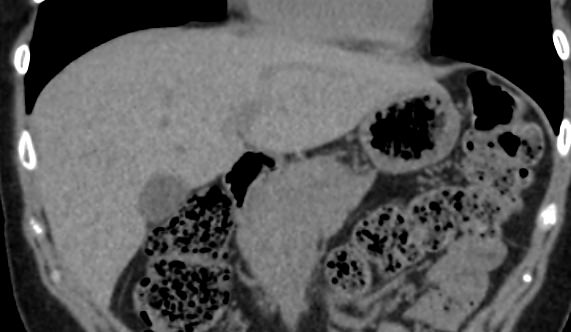

Мультиспиральная компьютерная томография желчного пузыря применяется для оценки состояния стенок желчного пузыря, изучения содержимого его полости, выявления воспалительных изменений, конкрементов и опухолевых новообразований.

В клинике «Доступная медицина» исследование проводится на новейшем 128-срезовом томографе TOSHIBA AQUILION CXL, который позволяет проводить исследование за короткий промежуток времени при сниженной лучевой нагрузке. Посредством инновационных компьютерных программ томограф преобразует полученные данные в 3D-изображения желчного пузыря и желчевыводящих протоков. Это помогает диагностировать заболевания гепатобилиарной системы особенно при нетипичной клинической картине, когда при помощи других методов обследования (УЗИ, МРТ) не удается выявить причину нарушения оттока желчи из желчного пузыря.

- камни желчного пузыря и его протоков;

- холангит и холецистит;

- абсцессы;

- нарушения кровоснабжения, травмы, кровоизлияния;

- воспалительные процессы в желчном пузыре и поджелудочной железе.